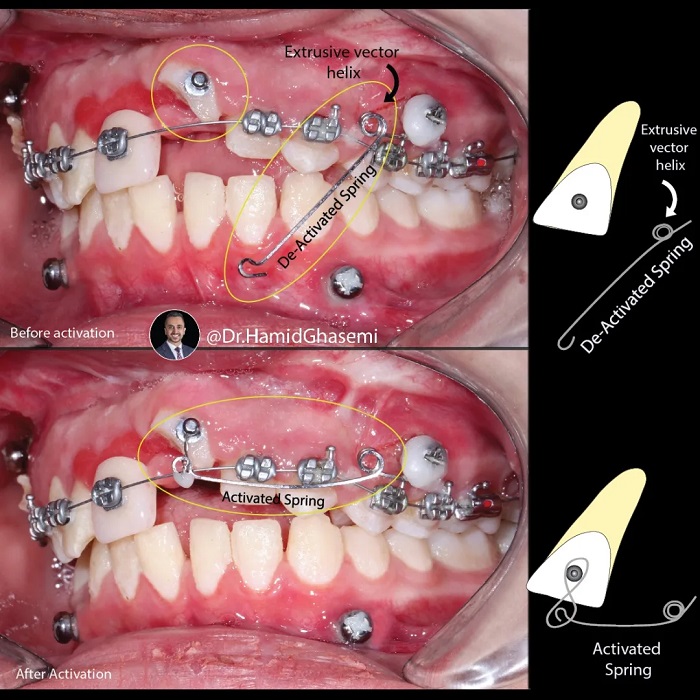

This is a case with history of traumatic accident to the face which caused Lefor I fracture + nasal bone fracture + multiple fractures of both arches + inrusive displacement of front teeth. Thanks to my dear friend @drkianiofficial for taking care of all surgical procedures which includes fixation of Lefort I and multiple fractures within the arches + nasal bone repair simultaneously and reffering the case for post surgical orthodontic force eruption of front teeth. Cantilever spring with double extrusive helix anchored to the surgical screw used to apply extrusive force to the front teeth. Take note on 👉👉 1.The distance of helix to the achorage unit (surgical screw), 2. Orientation of helix and 3.The distance of spring hook to the upper central incisor before activation which are the 3 key points of spring design